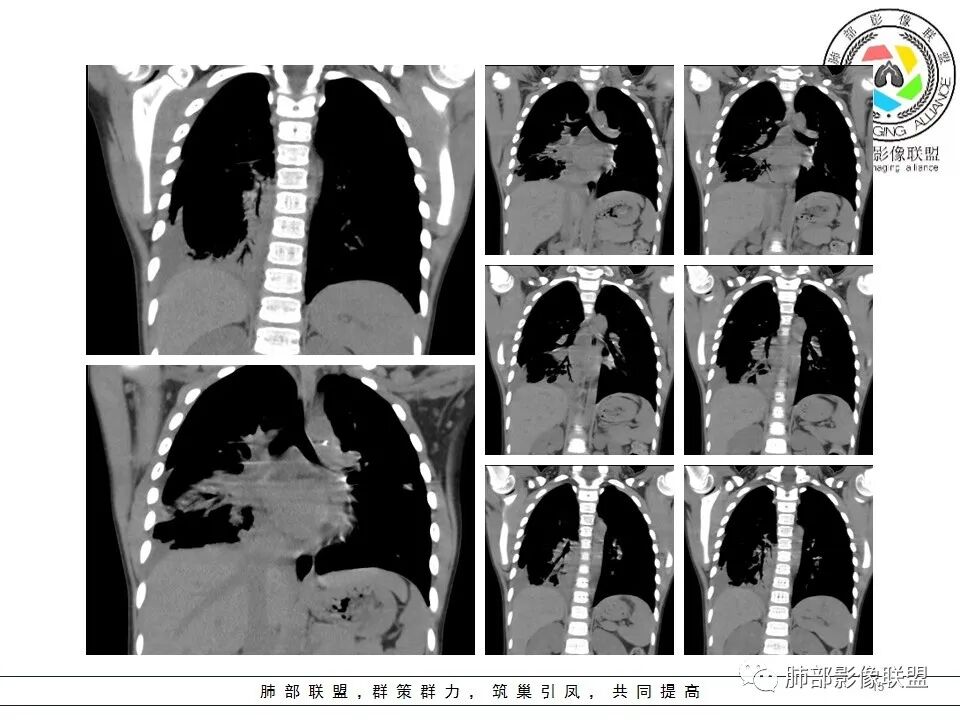

一切∮随缘: 前纵隔偏右侧实性占位,向右肺挤压,右肺膨胀不全,右侧胸水,心包似乎也有胸水,病灶较大无增强,平扫密度欠均匀,内部似可见低密度坏死及高密度钙化影,年轻男性,考虑恶性,生殖细胞肿瘤(精原细胞瘤?恶性畸胎瘤?),鉴别神经母细胞瘤,肺母细胞瘤,PNET?

秦化君: 右前上纵隔软组织密度肿块,边缘部分清晰澎隆,与血管及心包间界线不清,密度较均匀。挤压相邻肺组织形成膨胀不良,侵及胸膜形成胸腔积液。双肺内见随机分布结节。考虑纵隔恶性占位(肺及胸膜转移),生殖细胞瘤,畸胎瘤,淋巴瘤。建议穿刺活检。

放射线 (王秀仙): 右侧前纵膈巨大肿块,与纵膈大血管分界不清并受压,右肺组织受压膨胀不全,密度不均,内可见高密度钙化及低密度坏死区,双肺多发结节状转移灶,右侧胸腔积液,年轻男性,考虑生殖细胞肿瘤,精原细胞瘤可能性大。

宇宙: 男性小孩,右前纵膈不规则肿块,与心脏及大血管分界不清,邻近肺组织受压,其内可见钙化及低密度坏死,两肺多发类圆形结节,右侧胸水,考虑精原细胞瘤伴两肺及胸膜转移,鉴别恶性畸胎瘤。

金豆 (刘权威): 病灶主体位于纵隔,密度不均,内可见点状钙化灶,邻近肺组织受限不张,两肺散在结节,右侧胸水,9岁,恶,生殖类,恶性畸胎瘤,鉴别精原。

放射小白: 男9岁,胸痛,定位右前纵隔占位,内部可见钙化灶,右肺局部实变,两肺散在结节灶,右侧胸腔少量积液,常规考虑生殖类肿瘤,精原细胞瘤伴两肺转移,请结合实验室检查。

良孑: 右侧前纵膈巨大肿块,与纵膈大血管分界不清并受压,右肺组织受压膨胀不全,密度不均,内可见高密度钙化及低密度坏死区,坏死边界不清,双肺多发结节状转移灶,右侧胸腔积液,定性恶性,考虑生殖细胞肿瘤,精原细胞瘤或内脏窦瘤可能性大。

位移: 右侧前纵膈巨大肿块,内可见钙化及坏死区,两肺多发结节状转移灶,右侧胸腔积液,儿童,男,考虑生殖细胞肿瘤,精原细胞瘤可能性大,其次恶性畸胎瘤,外周性原始神经外胚层肿瘤。

蔡磊: 男孩,9岁,胸痛10天就诊。前纵隔偏右侧巨大肿块,内见点状钙化,与周围大血管结构不清,推移挤压。右肺受压,节段性不张。增强后双肺内多发类圆形实性结节。恶性病变肺内转移,生殖可能。

病理结果

生殖源性肿瘤(卵黄囊瘤+畸胎瘤)

二.影像表现:

右前纵隔巨大软组织肿块,主要偏向右侧生长,边界不清,密度不均匀,内见大片状低密度坏死区及散在钙化灶,未见骨骼影及脂肪密度影。、双肺随机分布的转移瘤结节,右肺肺不张及右侧胸腔积液,提示恶性肿瘤病变伴双肺及胸膜转移。